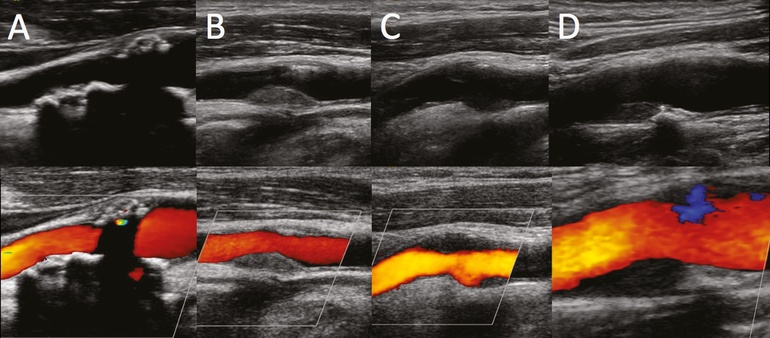

Ультразвуковое исследование (УЗИ) является первым и наиболее распространенным методом диагностики заболеваний общей сонной артерии. Этот неинвазивный метод позволяет визуализировать сосуды, оценить их проходимость, а также выявить наличие атеросклеротических бляшек и стенозов. УЗИ может быть выполнено с допплеровским исследованием, что позволяет оценить скорость кровотока и выявить нарушения гемодинамики.